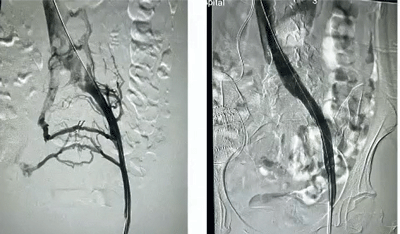

Collateral veins (left) disappear after a stent.

When a vein becomes compressed or blocked in the pelvis (or other areas), the body produces a tangle of small collateral veins in an attempt to maintain blood flow. While collateral veins can often help move blood and thereby relieve symptoms, they can also press on nerves or other structures, causing pain.

A short stent doesn’t work (middle image), but when a longer stent was put in (right image) and blood flow was restored and the collateral veins disappeared, the patient’s pain disappeared.

Her pelvic venography showed “severe obstruction of the left common iliac vein with near-complete flow arrest” and the development of numerous collateral veins. Stenting resulted in a significant reduction of her orthostatic symptoms as well as her pain, leg swelling, etc.

A pelvic ultrasound was normal, but an MRV found “severe compression” of both the left iliac and left renal veins, indicating that she had both May-Thurner syndrome and Nutcracker syndrome. Stenting of her left iliac vein resulted in a complete resolution of her POTS and concentration symptoms.